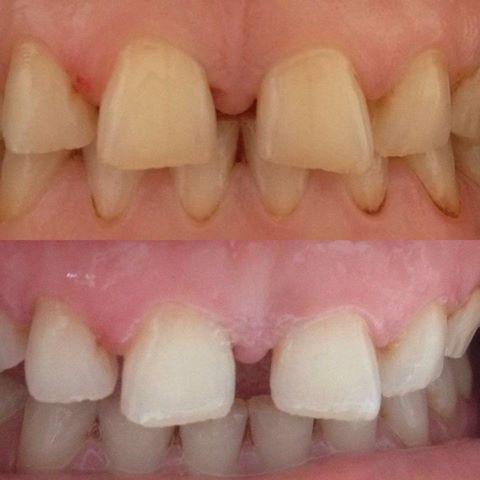

Diş implantı eksik olan diş veya dişlerin yerine yerleştirilen titanyumdan yapılmış yapay bir diş köküdür.